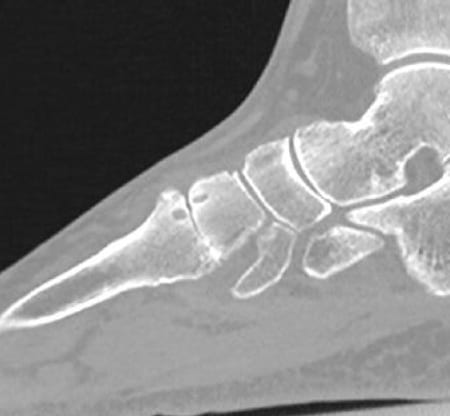

CT präoperativ

Zur Verifizierung der Arthrose.